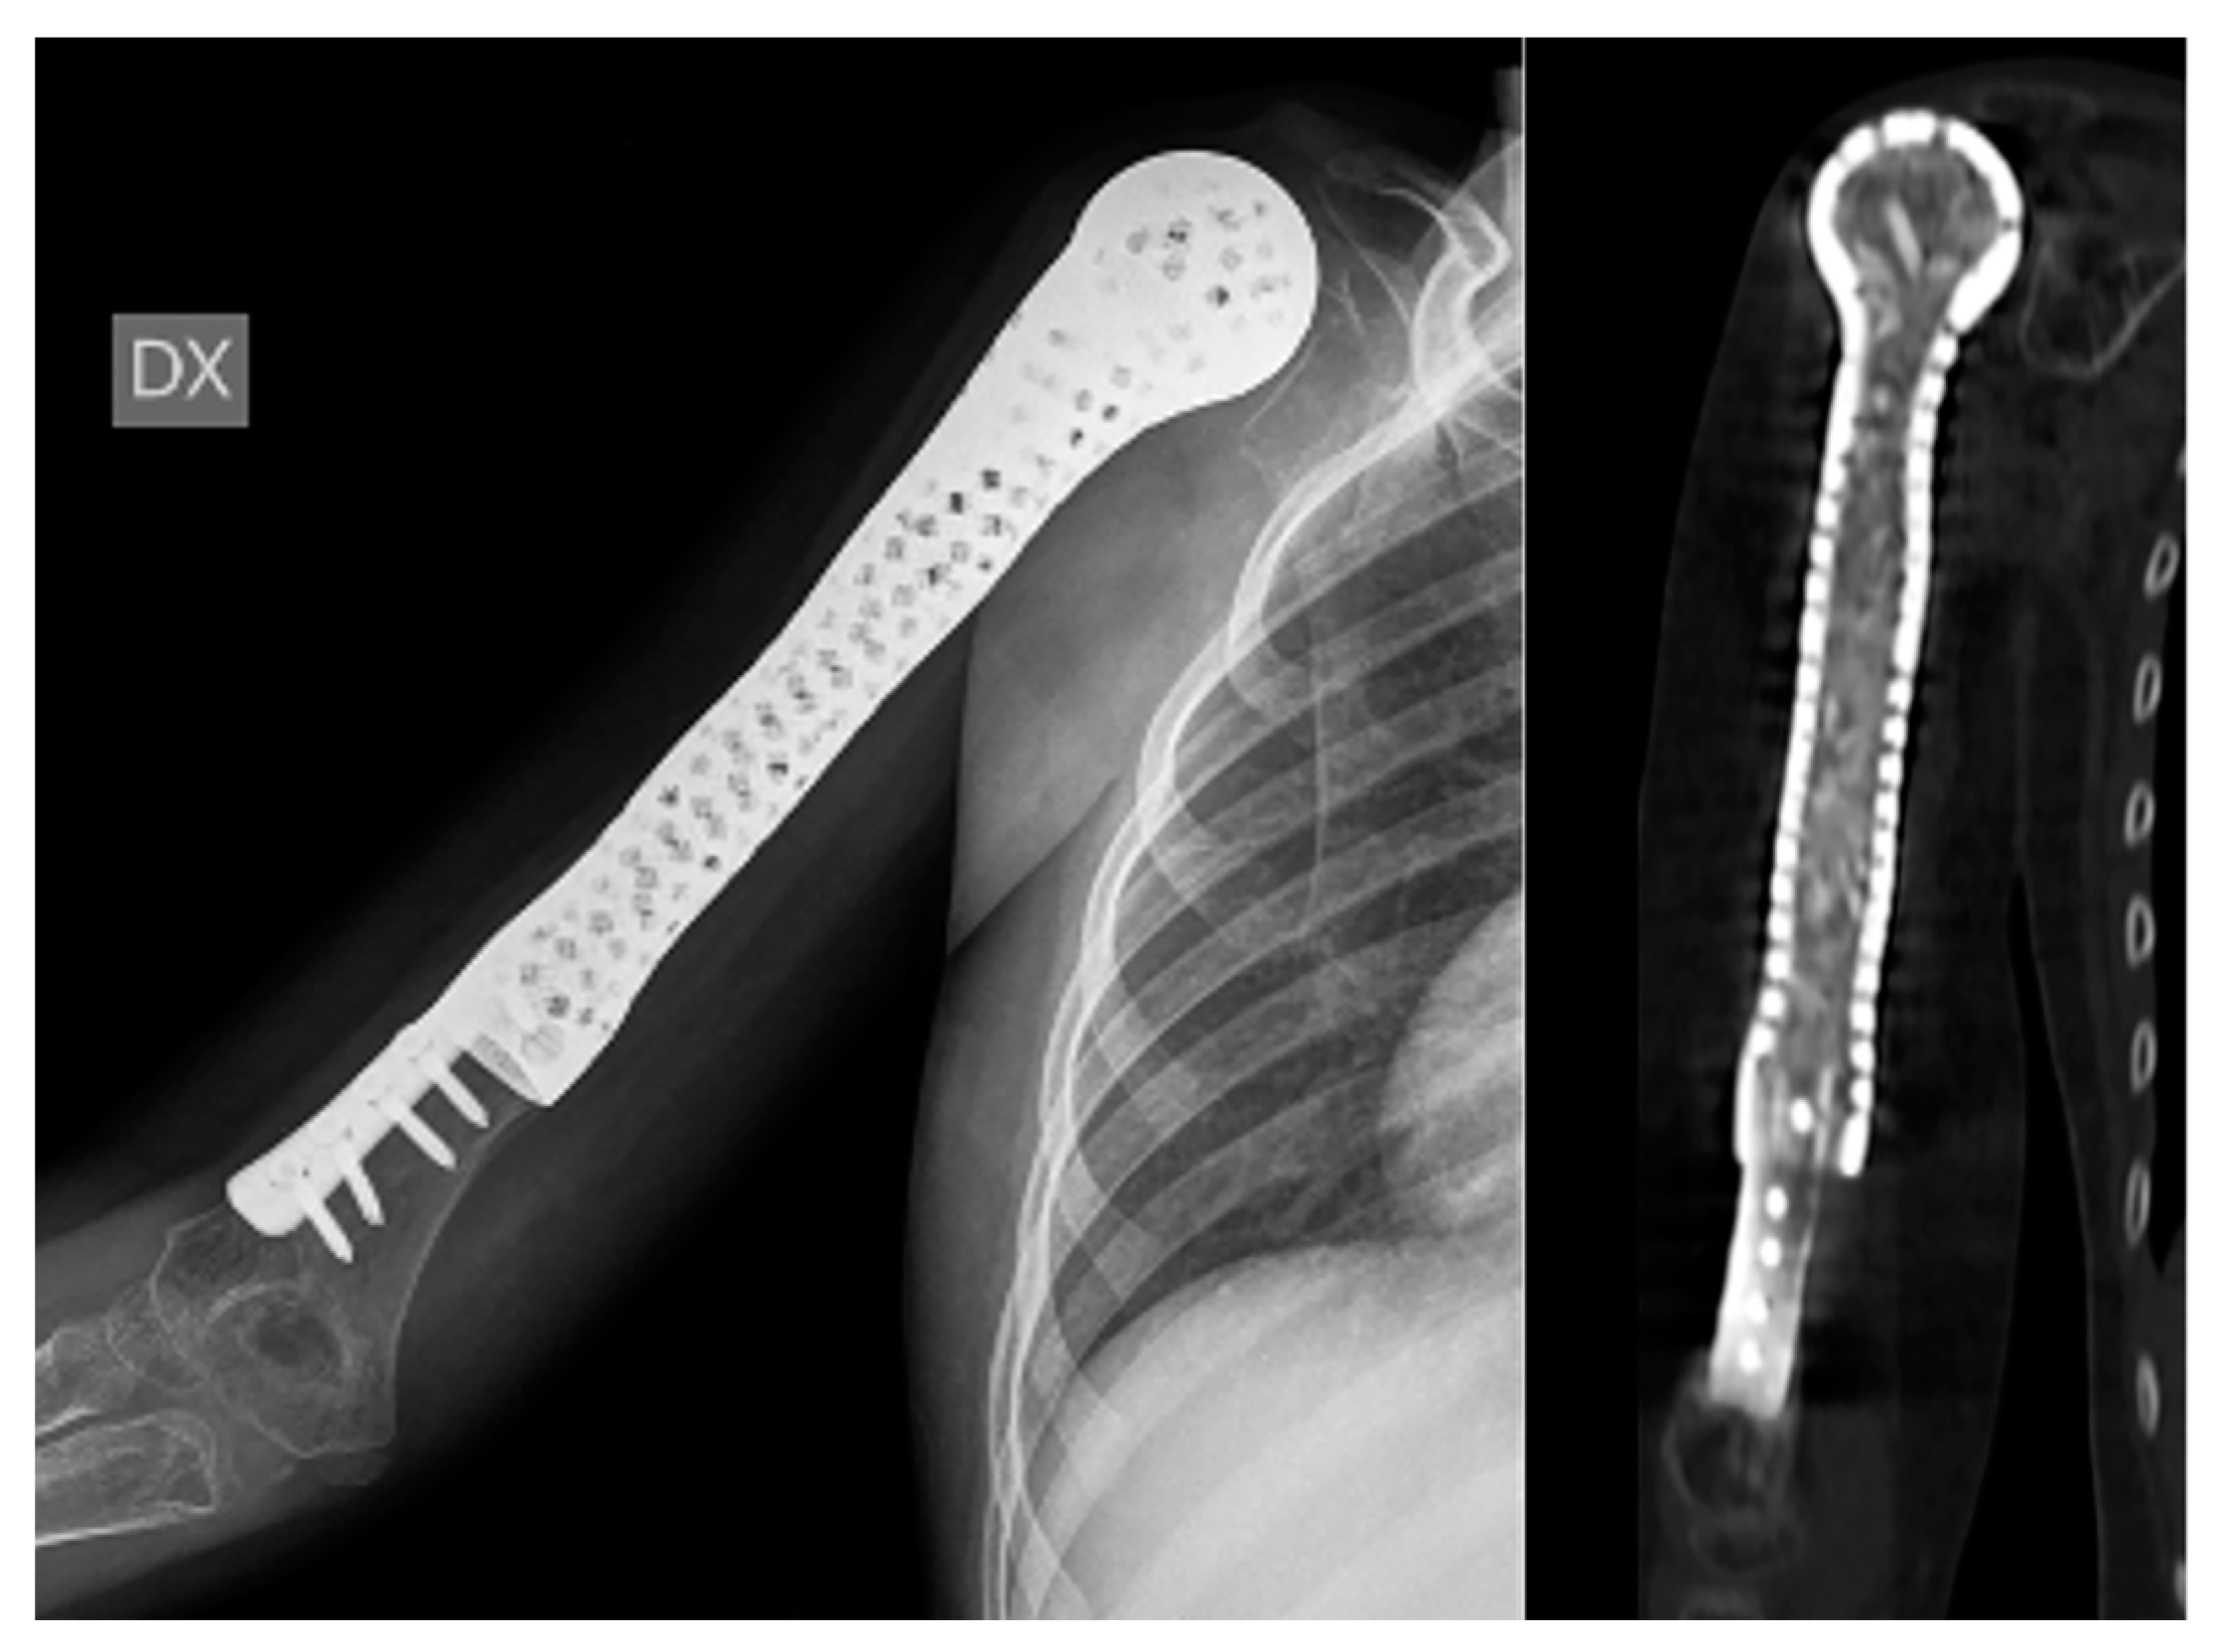

Biological Prosthesis (Hollow 3D-Printed Titanium Custom-Made Prosthesis and Bone Graft) for Humeral Reconstruction in Pediatric Oncologic Patients: Surgical Indications and Results

- Beltrami, G.; Ristori, G.; Nucci, A.M.; Galeotti, A.; Tamburini, A.; Scoccianti, G.; Campanacci, D.; Innocenti, M.; Capanna, R. Custom-made 3D-printed implants as novel approach to reconstructive surgery after oncologic resection in pediatric patients. J. Clin. Med. 2021, 10, 1056. [Google Scholar] [CrossRef] [PubMed]

- Beltrami, G.; Ristori, G.; Galeotti, A.; Scoccianti, G.; Tamburini, A.; Campanacci, D.; Capanna, R.; Innocenti, M. A hollow, custom-made prosthesis combined with a vascularized flap and bone graft for skeletal reconstruction after bone tumour resection. Surg. Oncol. 2021, 36, 56–60. [Google Scholar] [CrossRef]

- Beltrami, G.; Nucci, A.M.; Tamburini, A.; Innocenti, M. Custom-made 3D-printed prosthesis and free vascularised fibula for humeral reconstruction after osteosarcoma resection in a 13-year-old patient. BMJ Case Rep. 2021, 14, e240726. [Google Scholar] [CrossRef]